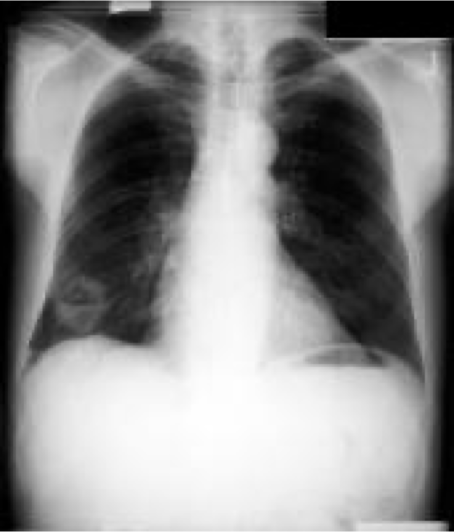

Normal CXR (PA & Lateral)